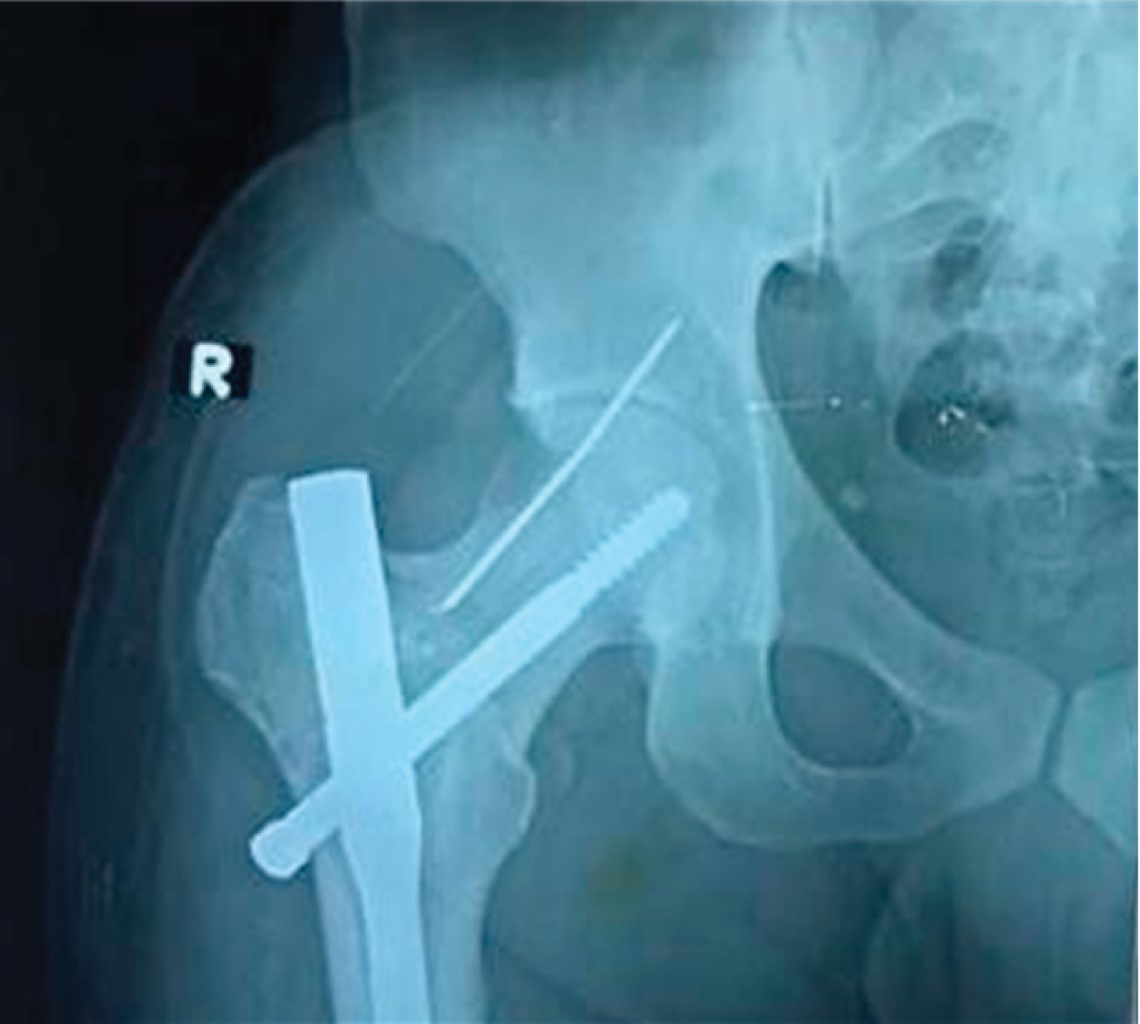

Implant related complications like screw back out (Figure 1), guide wire breakage (Figures 2 and 3), Z effect (Figure 4), TAD outliers (Figure 5) were more in PFN group whereas lateral screw protrusion, locking mechanism failure and barrel disengagement was more in PFNA2 group as shown in Figures 6, 7, 8 and 9. Neck shaft valgus outliers are more common in PFN group (Figure 10).

Nikoloski et al recommended a tip apex distance (TAD) of 20-30mm for PFNA2,25 observing a higher incidence of cut-through when TAD was more than 30 mm or less than 20 mm. In our study, TAD outliers (< 20 or > 30) were 9 and 11 in the PFN and PFNA2 groups, respectively, with a higher implant failure rate, which is consistent with the study by Sharma et al, who had more outliers in the PFNA2 group but fewer implant failures.26 Our results, supporting the study by Sharma et al., indicate that achieving an optimal TAD is crucial, but some outliers are acceptable in the PFNA2 group (as shown in Figure 5), likely due to its inherent stability.